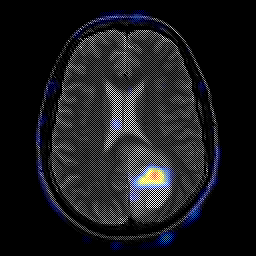

glioma overlay -- Slice #17

[Home][Help][Clinical] Slice 17